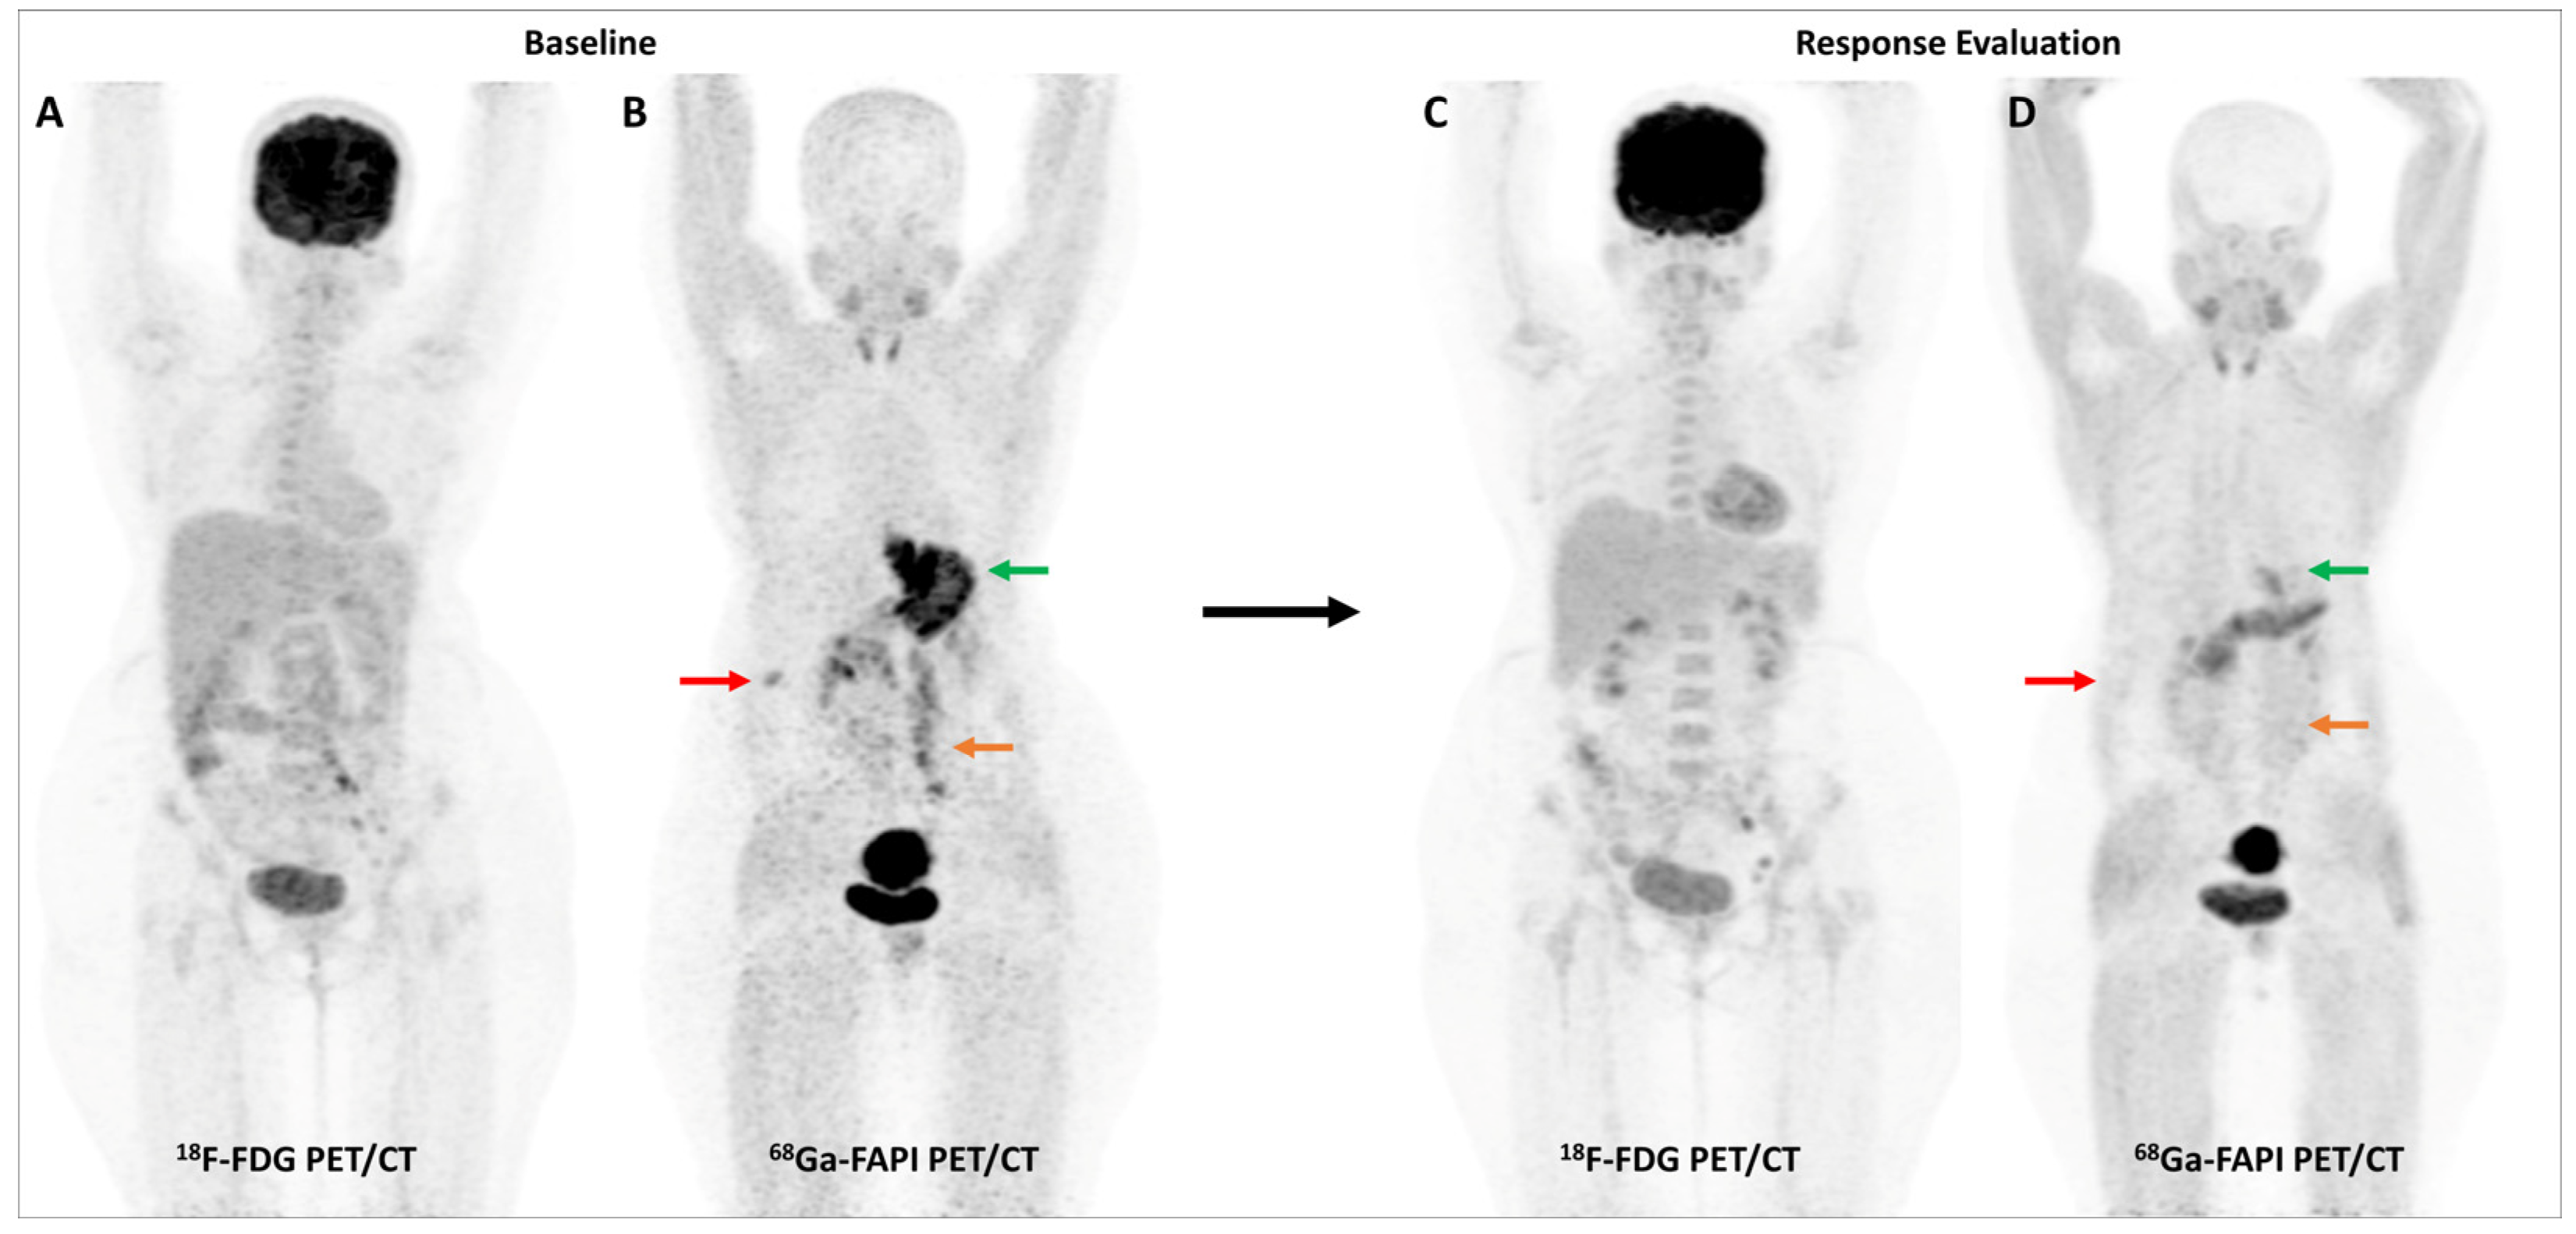

Multiple studies have consistently reported that FAP-targeted PET/CT imaging improves the detection of malignant peritoneal involvement, which is often challenging to pick up on conventional imaging [78,79]. A meta-analysis (including 11 studies and 340 patients) reported that [68Ga]Ga-FAPI PET/CT had significantly higher pooled sensitivity than FDG PET/CT for the detection of peritoneal metastases on both patient-based (98.2% vs. 55.9%) and lesion-based (99.9% vs. 27.3%) analyses [80]. Figure 5 highlights a representative case with peritoneal involvement.

Figure 5.

FDG and [68Ga]Ga-FAPI-04 PET/CT in a 33-year-old man with histopathologically proven mucinous adenocarcinoma of appendix post cytoreductive surgery, hyperthermic intraperitoneal chemotherapy, and platin-based adjuvant chemotherapy. FDG PET/CT (A) did not reveal significant abnormal tracer uptake. However, FAPI PET/CT (B) performed two days later revealed multiple tracer avid paracolic gutter, omental, peritoneal, and liver metastases (green arrows). Palliative chemotherapy with capecitabine and oxaliplatin was started. Subsequent response assessment was performed after 3 cycles of this second-line chemotherapy. FDG PET/CT (C) underestimated disease burden when compared with FAPI PET/CT (D), which showed few new peritoneal deposits (red arrows) in addition to pre-existing lesions (green arrows), suggestive of disease progression. This impacted management as the patient was started on third-line agents, irinotecan and panitumumab.